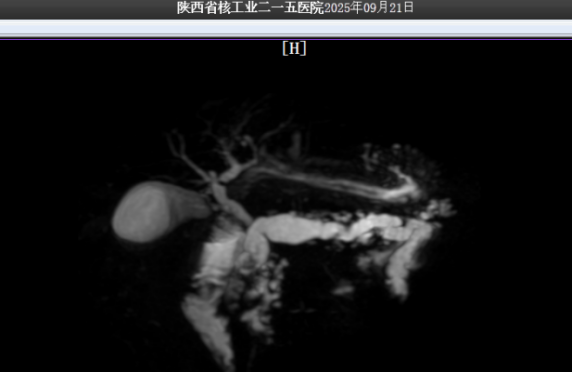

这些藏在翟先生体内的顽石,不仅体积巨大,而且位置极度刁钻。如果采用开腹取石的传统手术方式,非但创伤面积难以缩小,更存在其他伴生风险。本着不给翟先生增加痛苦与负担的初衷,普外一科联合碎石中心、手麻科和功能科举行多学科联合评估。得益于功能科与影像科的精确定位,翟先生体内结石大小、位置与胰管情况被精准捕捉,在反复推敲病情后,普外一科最终决定创新治疗思路,在咸阳市首次采用“体外冲击波碎石+后续内镜取石”的个体化微创治疗方案,这也是我院体外冲击波碎石技术,在泌尿系结石等常规治疗外,打击范围的再度扩张。

术后的超声复查显示,胰管内结石已被成功击碎,胰管明显通畅,患者状态恢复平稳,未出现胰腺炎急性发作等并发症,现已顺利返回病房。